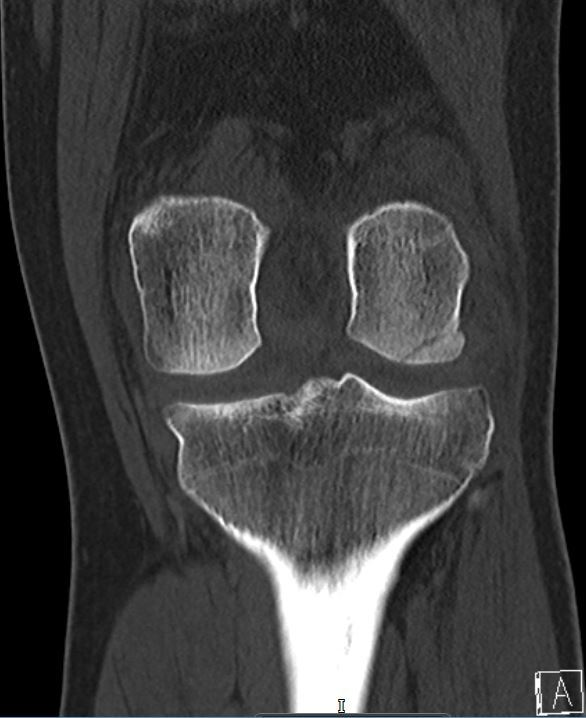

Computed tomography (CT) scan showed an OCF of the posterolateral femoral condyle (Figure 3 & 4). The MRI scan further confirmed the presence of an OCF of the lateral femoral condyle, and injury to the Medial Patellofemoral Ligament (MPFL), the latter is a secondary restraint to patella dislocation (Figure 5 & 6).

Figure 4 Coronal CT Scan view showing lateral femoral condylar osteochondral fracture.